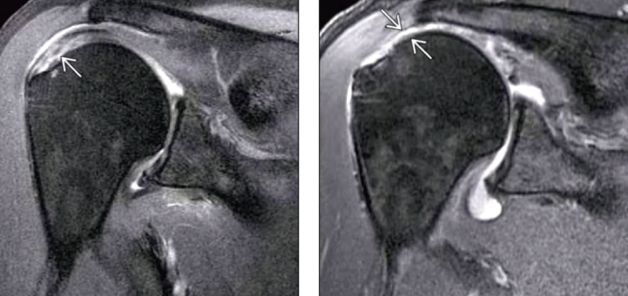

¿Cómo se ve el desgarro de manguito rotador en RM?

Hiperintensidad en T2

Q

Desgarro de manguito rotador

• Desgarros pequeños

• Lesión de múltiples estructuras: ligamentos, cartílago, labrum, etc

• ArtroRM detecta lesiones ligamentarias